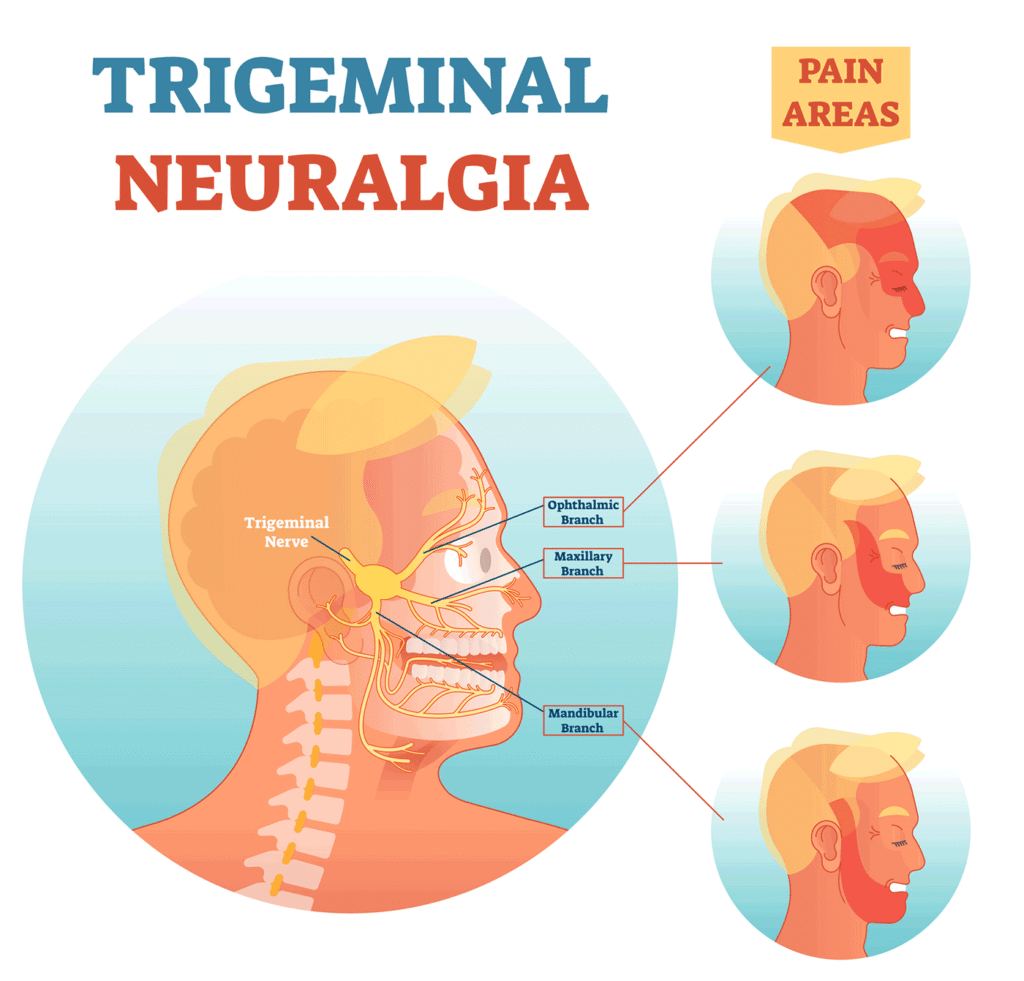

Trigeminal Neuralgia and Acupuncture: A Comprehensive Guide

Trigeminal neuralgia (TN), often referred to as the “suicide disease” due to its excruciating facial pain, is a chronic neurological condition that affects the trigeminal nerve—one of the most critical and widely distributed nerves in the head. The condition is notorious for causing sudden, severe, electric-shock-like pain that can be triggered by even the lightest […]

Acupuncture for Trigeminal Neuralgia: A Comprehensive Guide to Pain Relief in Tokyo

Trigeminal neuralgia (TN) is a chronic pain condition that affects the trigeminal nerve, causing intense, electric-shock-like pain in the face. Often described as one of the most excruciating pain syndromes, TN can significantly impact quality of life, making everyday activities like eating, speaking, or even brushing teeth unbearable. While conventional treatments like medications and surgery […]